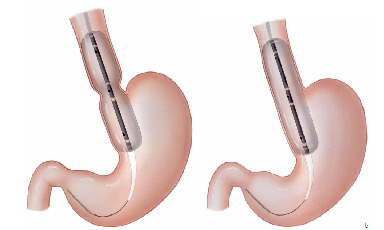

Pacientes que têm o objetivo de emagrecer, podem ter como alternativa a passagem de um balão intragástrico. A passagem do balão é realizada por endoscopia e o procedimento dura cerca de 20 a 30 minutos.

Passagem de Balão Intragástrico

1. O balão intragástrico é introduzido desinsuflado durante a endoscopia e colocado no estômago.

2. Um líquido azul (azul de metileno diluído em soro fisiológico) é colocado dentro do balão através de uma válvula. O volume varia entre 500-700 ml.

3. O aparelho de endoscopia é removido e o balão intragástrico pode ser deixado por um período de até 6 meses.

O balão intragástrico ocupa um espaço dentro do estômago e o paciente fica com sensação de plenitude e saciedade precoce. Em outras palavras, sobra menos espaço para os alimentos, diminuindo o volume ingerido nas refeições.

Pacientes que têm o objetivo de emagrecer, podem ter como alternativa a passagem de um balão intragástrico. A passagem do balão é realizada por endoscopia e o procedimento dura cerca de 20 a 30 minutos.

Passagem de Balão Intragástrico

1. O balão intragástrico é introduzido desinsuflado durante a endoscopia e colocado no estômago.

2. Um líquido azul (azul de metileno diluído em soro fisiológico) é colocado dentro do balão através de uma válvula. O volume varia entre 500-700 ml.

3. O aparelho de endoscopia é removido e o balão intragástrico pode ser deixado por um período de até 6 meses.

O balão intragástrico ocupa um espaço dentro do estômago e o paciente fica com sensação de plenitude e saciedade precoce. Em outras palavras, sobra menos espaço para os alimentos, diminuindo o volume ingerido nas refeições.